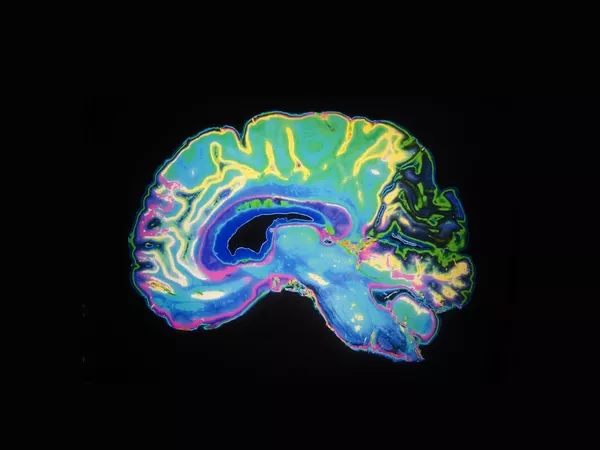

La relación intrincada entre nuestro cerebro y nuestras acciones ha fascinado a la humanidad durante siglos. ¿Cómo los procesos neuronales dan forma a todo lo que hacemos, desde el simple acto de levantar la mano hasta las complejas decisiones que definen nuestras vidas? Esta es la pregunta fundamental que aborda un campo vibrante y en constante evolución: la Neurociencia del Comportamiento.

Este campo, también conocido a veces como psicobiología, psicología biológica o neurociencia conductual, representa un puente esencial entre la psicología, que estudia la mente y el comportamiento, y la neurociencia, que se centra en el sistema nervioso. Su objetivo principal es comprender cómo las estructuras, funciones y procesos del cerebro y otras partes del sistema nervioso influyen en el comportamiento animal y humano.

¿Qué Estudia la Neurociencia del Comportamiento?

La Neurociencia del Comportamiento es increíblemente amplia y abarca una vasta gama de temas. Los investigadores en este campo exploran cómo el cerebro regula:

Para investigar estas cuestiones, los neurocientíficos del comportamiento emplean una variedad de métodos, que van desde estudios con modelos animales hasta técnicas avanzadas de neuroimagen en humanos, como la resonancia magnética funcional (fMRI) o la electroencefalografía (EEG). También utilizan estudios genéticos, farmacológicos y lesiones cerebrales (estudiando el impacto del daño en áreas específicas) para desentrañar los complejos circuitos neuronales.